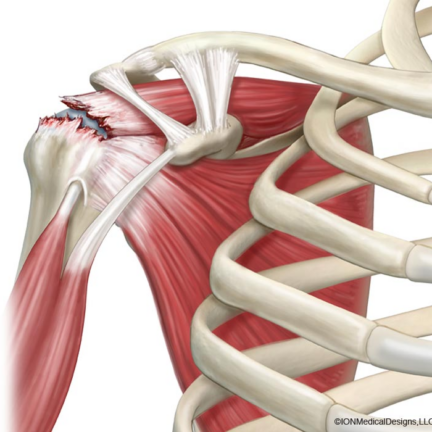

Rotator Cuff Tear